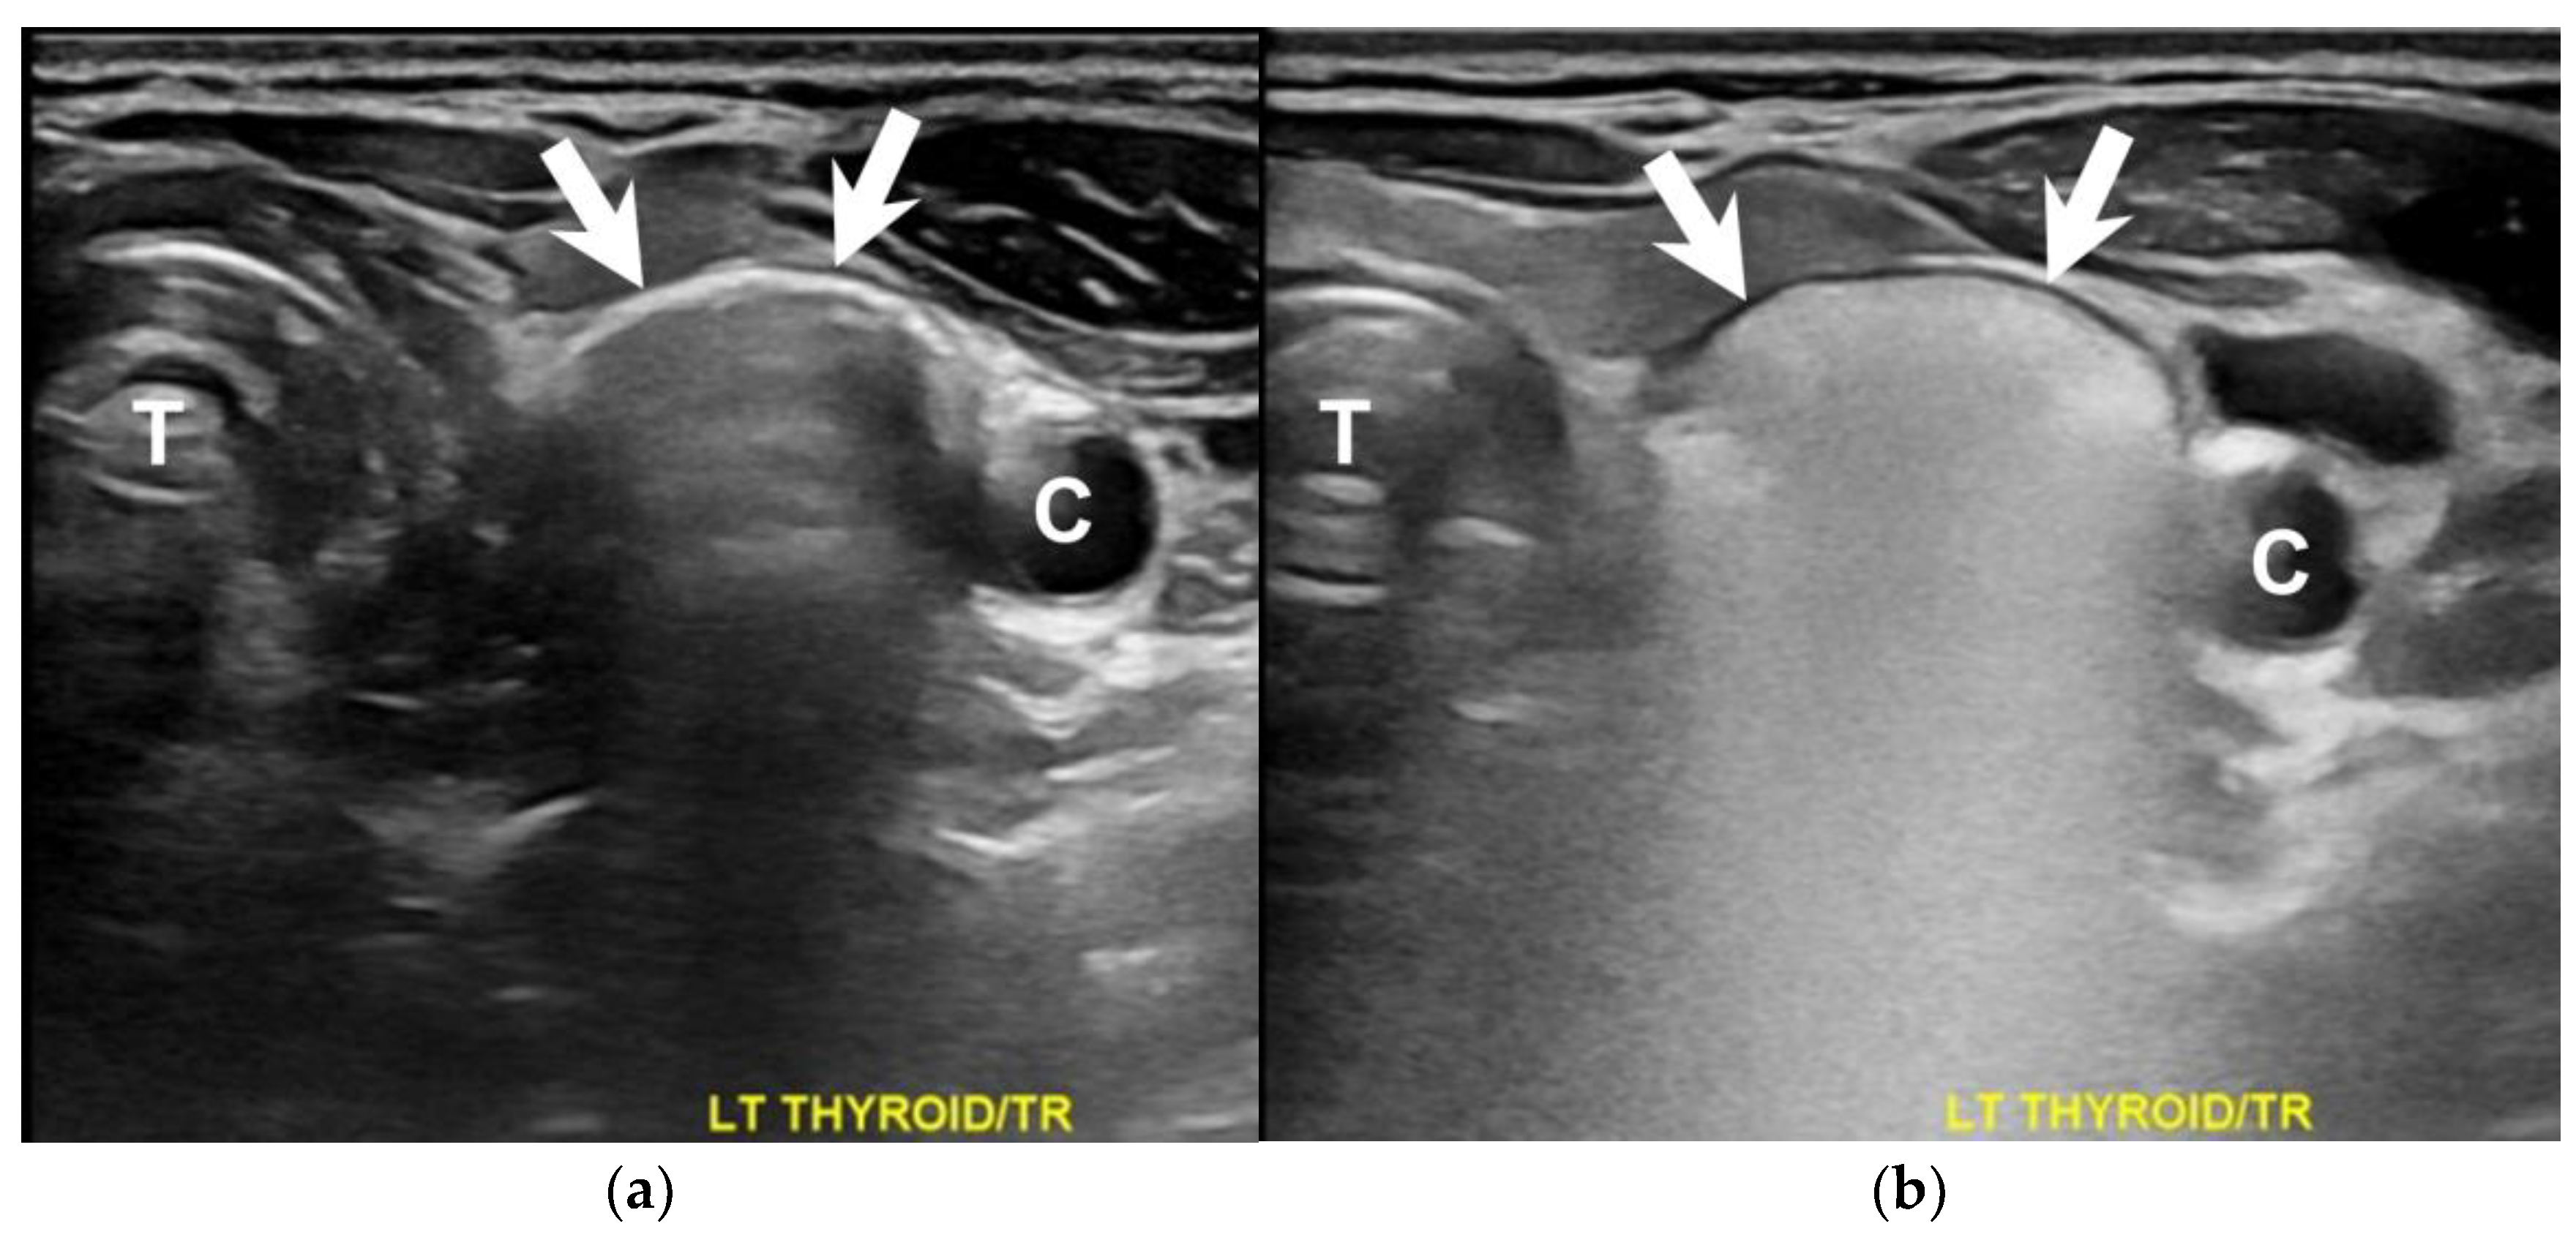

How Soda Ingestion Facilitates the Distinction between a Killian–Jamieson Diverticulum and a Malignant Thyroid Nodule